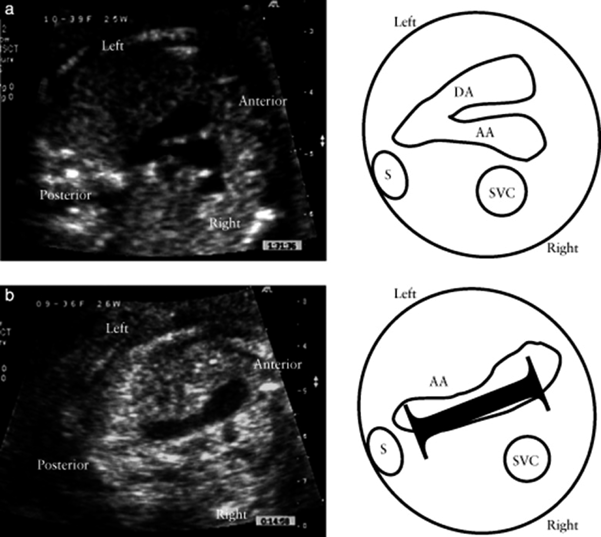

心内の形態異常を合併しない単独の総肺静脈還流異常(isolated TAPVC)は,四腔断面の異常がないため,TGAと同様,従来は胎児診断が困難な疾患とされていた.2003年にValsangiacomoらはTAPVCにおいて左房と下行大動脈に‘wide gap’があると述べ28),2006年にInamuraらはTAPVCの四腔断面ではLA後方に腔を二つ(共通肺静脈腔と下行大動脈)認める‘double balloon sign’を報告し29),2007年にBergらは‘the area behind heart’がCHD診断に重要であると報告した30).

そして2014年にKawazuらは,左房–下行大動脈間距離を下行大動脈径で除した値をPLAS indexとし,isolated TAPVCの胎児診断に有用と報告した20).具体的には,胎児isolated TAPVC8例と正常胎児101例において,PLAS index(=左房–下行大動脈間距離(LD)/下行大動脈径(DA))(Fig. 3)を比較したところ,TAPVC症例は有意に高値であり(p<0.0001),PLAS indexが1.27以上であるとTAPVCが疑わしいと報告した(感度100%,特異度99%).2016年にはAkkurtらが,在胎20~24週の正常胎児165例においてPLAS indexの計測を行い,その値が0.65+/−0.13と低値であったことと在胎週数による変動がなかったことを報告しており31),Isolated TAPVCの胎児診断に期待される指標と考えられる.ただ一方でPLAS index低値であった偽陰性例の報告もある32)ことから,単独で使用するのではなく他の指標も合わせて診断することが必要かもしれない.